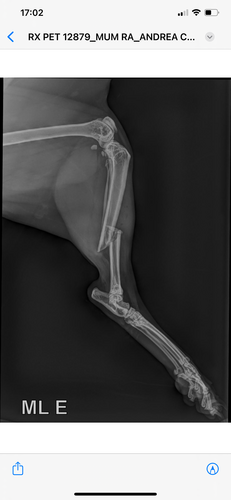

Este acidente ocasionou muitas lesões como: fratura de fêmur, deslocamento de bacia, fratura de cauda e perda de controle fisiológico.

Diante dessa situação, ele terá que passar por uma cirurgia de grande porte para estabilizar sua situação, nesta cirurgia ele colocará pinos na pata e removerá a cauda. Conseguimos um cartão de crédito para pagar as despesas mas está muito caro e precisamos de ajuda!